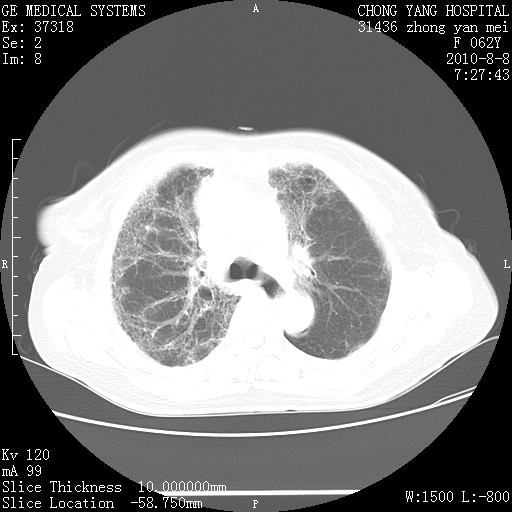

标题: CT28269:F62Y咳嗽胸痛数月。 [打印本页]

标题: CT28269:F62Y咳嗽胸痛数月。

两肺弥漫性间质纤维化伴继发性支扩。

考虑特发性肺间质纤维化

考虑两肺间质性肺炎并肺间质纤维化。

双肺间质纤维化合并感染、肺气肿

两肺间质纤维化并牵拉性细支气管扩张。

考虑两肺间质性肺炎并肺间质纤维化,肺气囊形成。

两肺间质改变,纵隔淋巴结肿大,需要考虑结节病的可能。